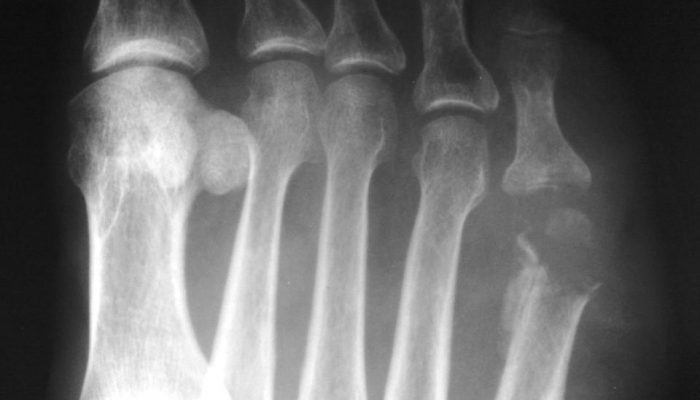

- Рентгенологическое в нескольких проекциях.

- Компьютерная и магнитно-резонансная томография (более современные и точные).

Эти методы исследования позволяют определить локализацию очага гнойного поражения, дифференцировать патологию мягких и костных тканей, диагностировать нежизнеспособные участки и т. д.

Признаки остеомиелита, выявляемые на томограммах и рентгенограммах:

- Сглаживание или исчезновение явного разделения губчатого и компактного вещества кости.

- Выявление очагов разрушения или разрежения костной ткани. Они обычно бывают округлой или овальной конфигурации.

- Изменение толщины и рельефа надкостницы.

- Появление секвестров любой формы и размеров.

Помимо этого, применяется ультразвуковое сканирование (в основном – для диагностики свищевых ходов), радионуклидные исследования, различные лабораторные анализы и другие методы.